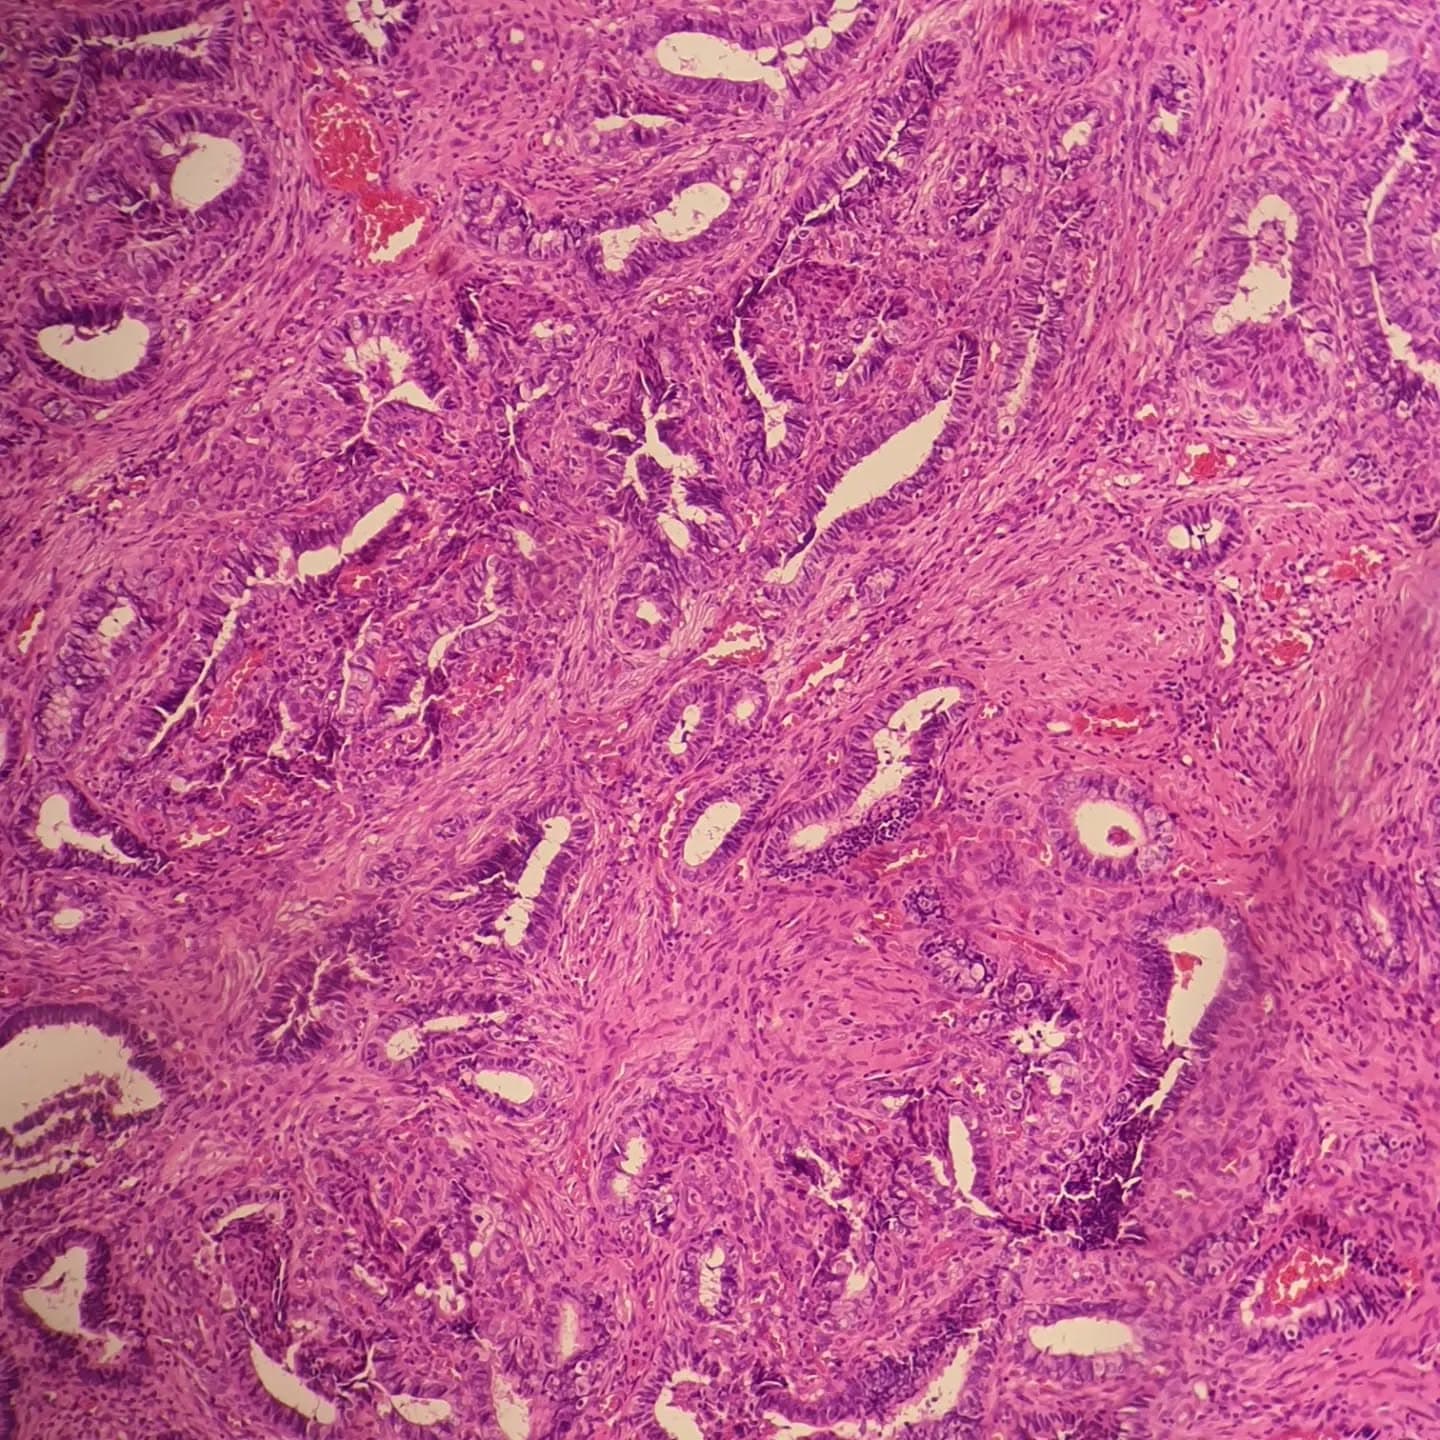

Caption: A 46 y/o female with complaint of AUB, sonographic exam showed an endocervical polyp with endometrial thickness of 7mm, and here it is, the amazing "atypical polypoid adenomyoma (APA)": lobular architecture in low power, biphasic lesion composed of endometrioid glands with complex architecture in a fibromyomatous stroma and very common squamous morules. @taghipoursalameh